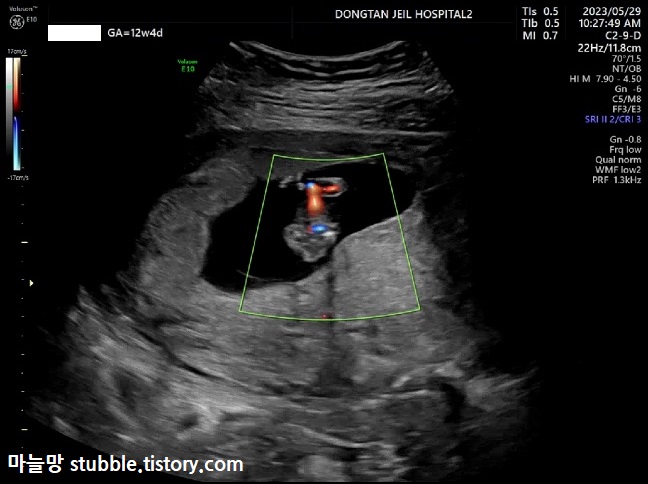

이거는 잘 생각이 안 나지만, 모체에서 아기에게 전달되는 혈류체크 같은 건가 봐요. 저에게로부터 아기에게까지 잘 전달되는 혈류의 이동상태?를 볼 수 있어요.

성별을 예측해 볼 수 있다는 각도법의 자세인 것 같은데 각도법은 볼 줄 모르옵니다.